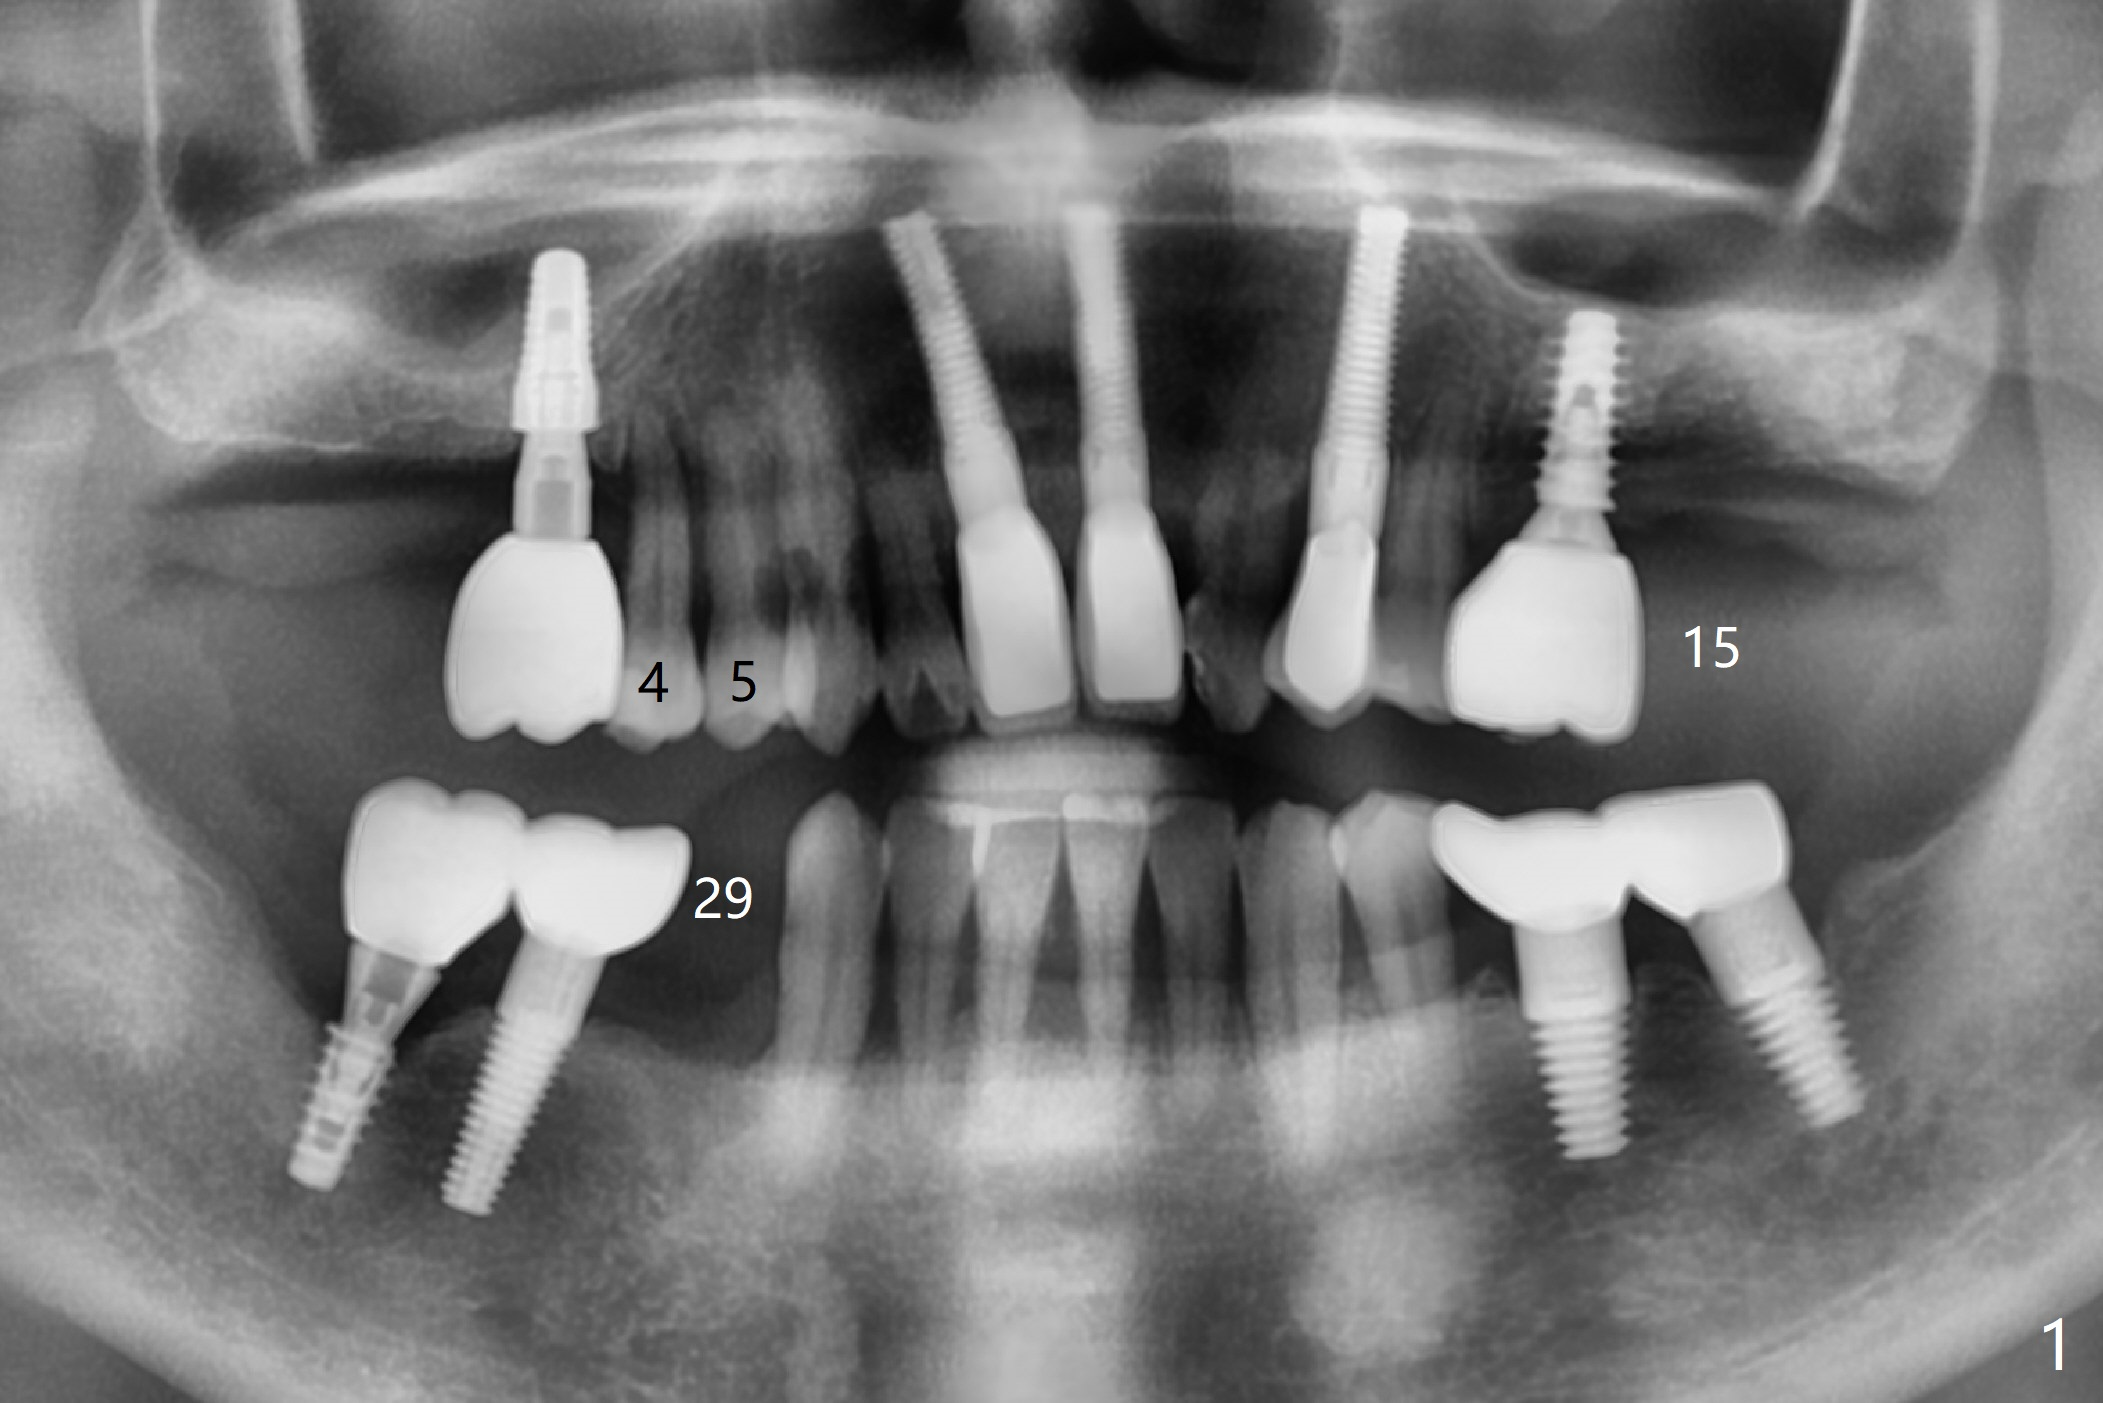

A 46-year-old man requests immediate implants at #4 and 5 because of pain associated with advanced periodontitis. Implants at #15 and 29 were removed with bone graft 4 months earlier (Fig.1). All of the 4 implants will be placed with guide. When 3.5 mm implants are placed at #4 and 5, they appear to be too close to each other (Fig.2). It is alright when the diameter changes to 3.0 mm (Fig.3). While a 5x10 mm implant will be placed at the 2nd stage (Fig.4), a 4x11.5 mm one will be placed in the same appointment as #4 and 5 (Fig.5).